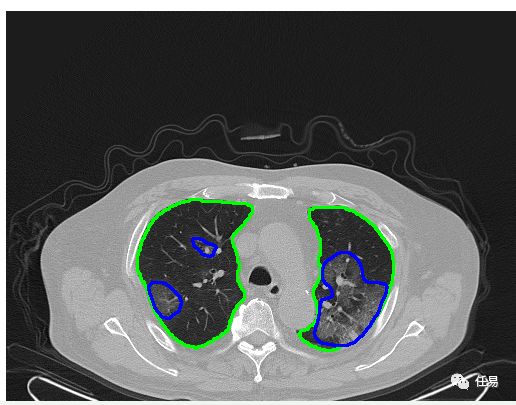

另外,钟南山院士还提到,在临床诊断上,超过85%患者出现胸部CT异常,毛玻璃样改变(GGO)或双侧浸润最为常见。但也有一些无症状患者,没有CT异常。钟院士团队收集了超过44000的病例,特别是危重患者中的病死率达到49%。

所以应书记到任后,要求把临床诊断病人(CT)也纳入方舱医院的治疗范畴,然后进一步进行抗体检测,真正做到了应收尽收,这就有效控制了疫情。

AI识别CT的原理,其实就是把图片进行切割,然后进行卷积,识别边缘,包括识别颜色,就是我们熟知的大白肺,所以只要有了足够的、经过标注的图像数据,我们就能用AI识别出来。

2月21日,阿里达摩院发布了AI诊断,在湖北、上海、广东、江苏等16个省市部署了26家医院,并对3万个临床疑似新冠肺炎病例CT影像进行了诊断,可以在20秒内完成评定准确率达到96%;